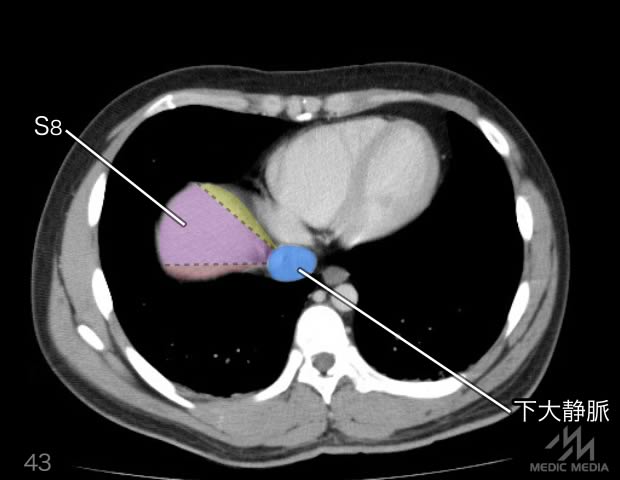

造影CT

消化器

肝区域